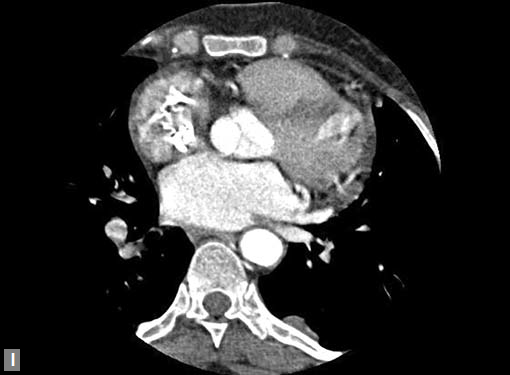

Figs 19A to Y (A to C) Scannogram (A), plain (B) and contrast study (C) show partial anomalous pulmonary venous connection; (D to F) Heterotaxy; (G) Aortic occlusion; (H and I) Aortic stents; (J) Aortic dissection with ‘Benz’ sign due to second dissection within the true lumen; (K, L and M) Aortic dissection with thrombus in pseudolumen following catheter angiogram; (N) Aortic dissection involving common carotid arteries and subclavian artery; (O, P, Q and R) Aortic dissection with right renal artery arising from true lumen and left renal artery from false lumen; (S, T, U and V) Stanford B dissection with extension Y to iliac vessels; (W to Y) Aneurysmal dilation of ascending aorta